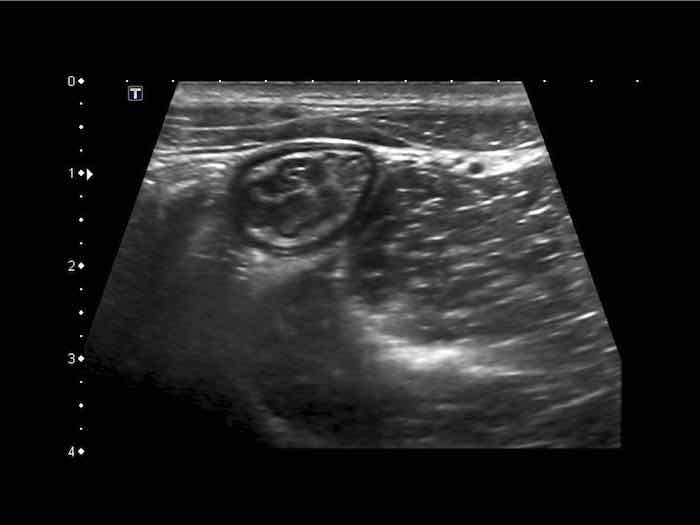

Hình ảnh siêu âm kinh điển của lồng ruột hồi-manh tràng ở hai trẻ khác nhau.

Trong cả hai trường hợp, đoạn hồi tràng bị lồng được định vị không đối xứng bên trong ống lồng ngoài, do mạc treo ruột tăng âm có chứa mỡ, bám vào hồi tràng và đi theo hồi tràng khi bị kéo vào trong.

Trong mạc treo, siêu âm cho thấy một hạch bạch huyết mạc treo (hbh) phóng đại ở cả hai.

Các hạch này phì đại như một phần của tình trạng tăng sản hạch bạch huyết toàn thân và khônghu trú trong lòng hồi tràng.

Do đó đây không phải là điểm dẫn đầu nguyên phát. Ở bệnh nhân bên phải, ruột thừa (mũi tên) cũng bị kéo vào trong.

Lưu ý cấu trúc đa lớp của thành bụng phía trước của phức hợp lồng ruột, đại diện cho ba lớp thành ruột bị gấp lại.